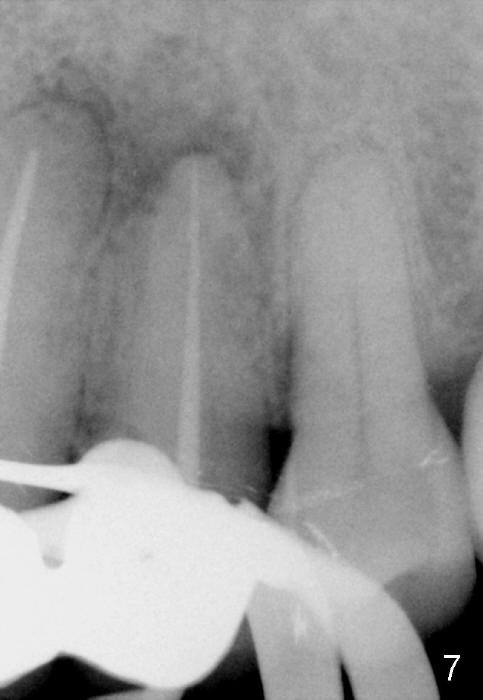

One month later, the fistula is regressing, while the pain reduces (Fig.4). It appears that the initial access is not extended lingually enough (Fig.5). The lingual canal is still non-negotiable when the access is enlarged (Fig.6). Working length of the buccal canal is confirmed with 30/.06 Gutta Percha in place (Fig.7). After explanation and consent, RCT is finished routinely. Two months postop, the buccal apical fistula resolves with no symptom (Fig.8). The retainer at the site of #12 is not removed to increase chance of finding the missing canal. It is part of a long bridge.